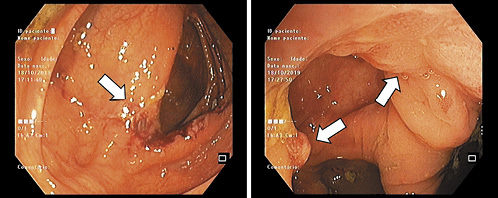

A decision was made to repeat colonoscopy with lesion sampling at our center. At this procedure, an area of irregular mucosa with approximately 15 mm adjacent to the ileocecal valve was observed (Fig. 1a). This lesion had a congestive appearance, with superficially ulcerated areas and a pseudo-polypoid component. On the hepatic flexure, additional areas of mucosa ranging from 5 to 10 mm with similar characteristics were seen (Fig. 1b). The remaining colon segments had no endoscopic abnormalities. The first endoscopic impression was of an ischemic or drug-induced colopathy, but the patient had neither a history of cardiovascular risk factors nor a regular consumption of drugs associated with colorectal mucosal disruption.

Fig. 1 a Endoscopic image of ileocecal valve lesion (white arrow). b Endoscopic image of hepatic flexure lesions (white arrows).